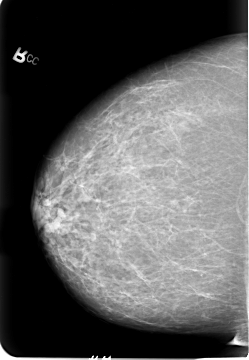

Volume: cancer_01 Case: B-3021-1

B_3021_1.LEFT_CC

LEFT_CC LINES 5704 PIXELS_PER_LINE 4080 BITS_PER_PIXEL 12 RESOLUTION 50 OVERLAY

FILE: B_3021_1.LEFT_CC.OVERLAY

TOTAL_ABNORMALITIES 3

ABNORMALITY 1

LESION_TYPE MASS SHAPE LOBULATED MARGINS CIRCUMSCRIBED-ILL_DEFINED

ASSESSMENT 3

SUBTLETY 3

PATHOLOGY MALIGNANT